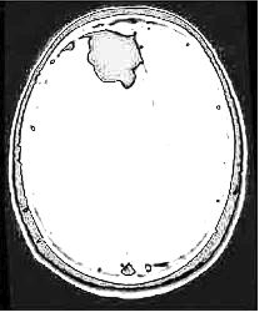

Table 6 Fused image output.

From: Multimodal medical image fusion combining saliency perception and generative adversarial network